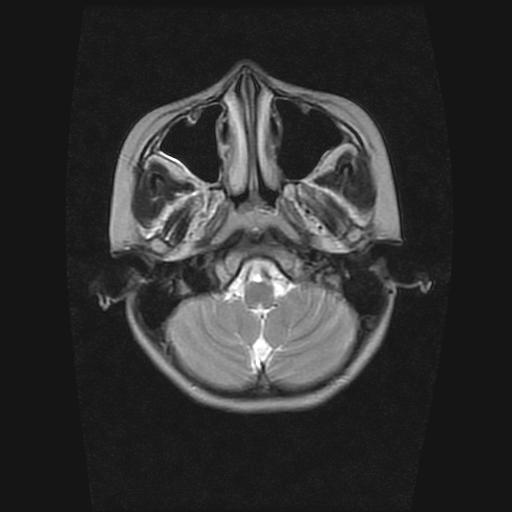

9岁女孩,三岁时诊断为癫痫,一直服丙戊酸钠,现患者一般情况良好,家长复查核磁片,看能否停药..

未发现异常信号。

未发现异常信号!

未发现异常信号。  停药要结合临床